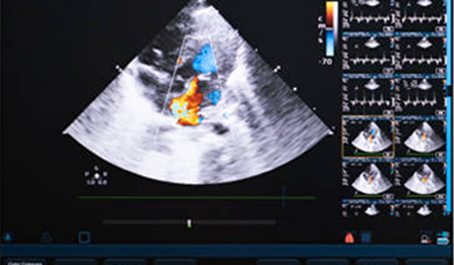

• Adult and Pediatric Echocardiogram (ECHO)

• Arterial, Venous and Carotid Doppler Studies

• Transesophageal electrocardiogram (TEE)